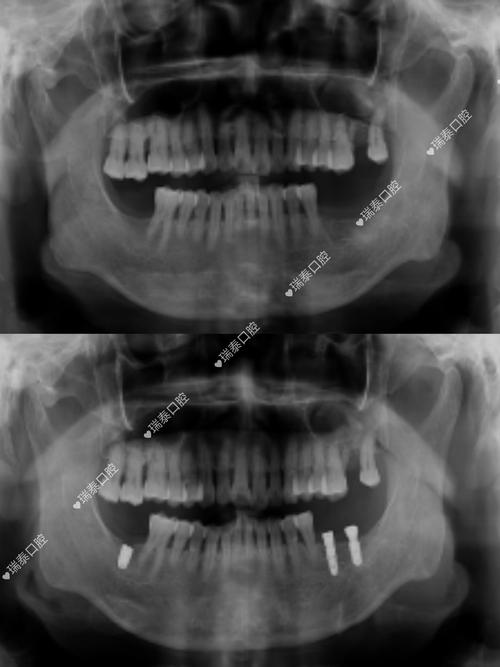

- 术后评估:

- 种植体位置: 确认种植体是否放置在理想位置。

- 骨结合情况: 观察种植体与周围骨组织是否良好结合(骨整合)。

- 并发症排查: 检查是否有感染、神经损伤、上颌窦穿孔等问题。